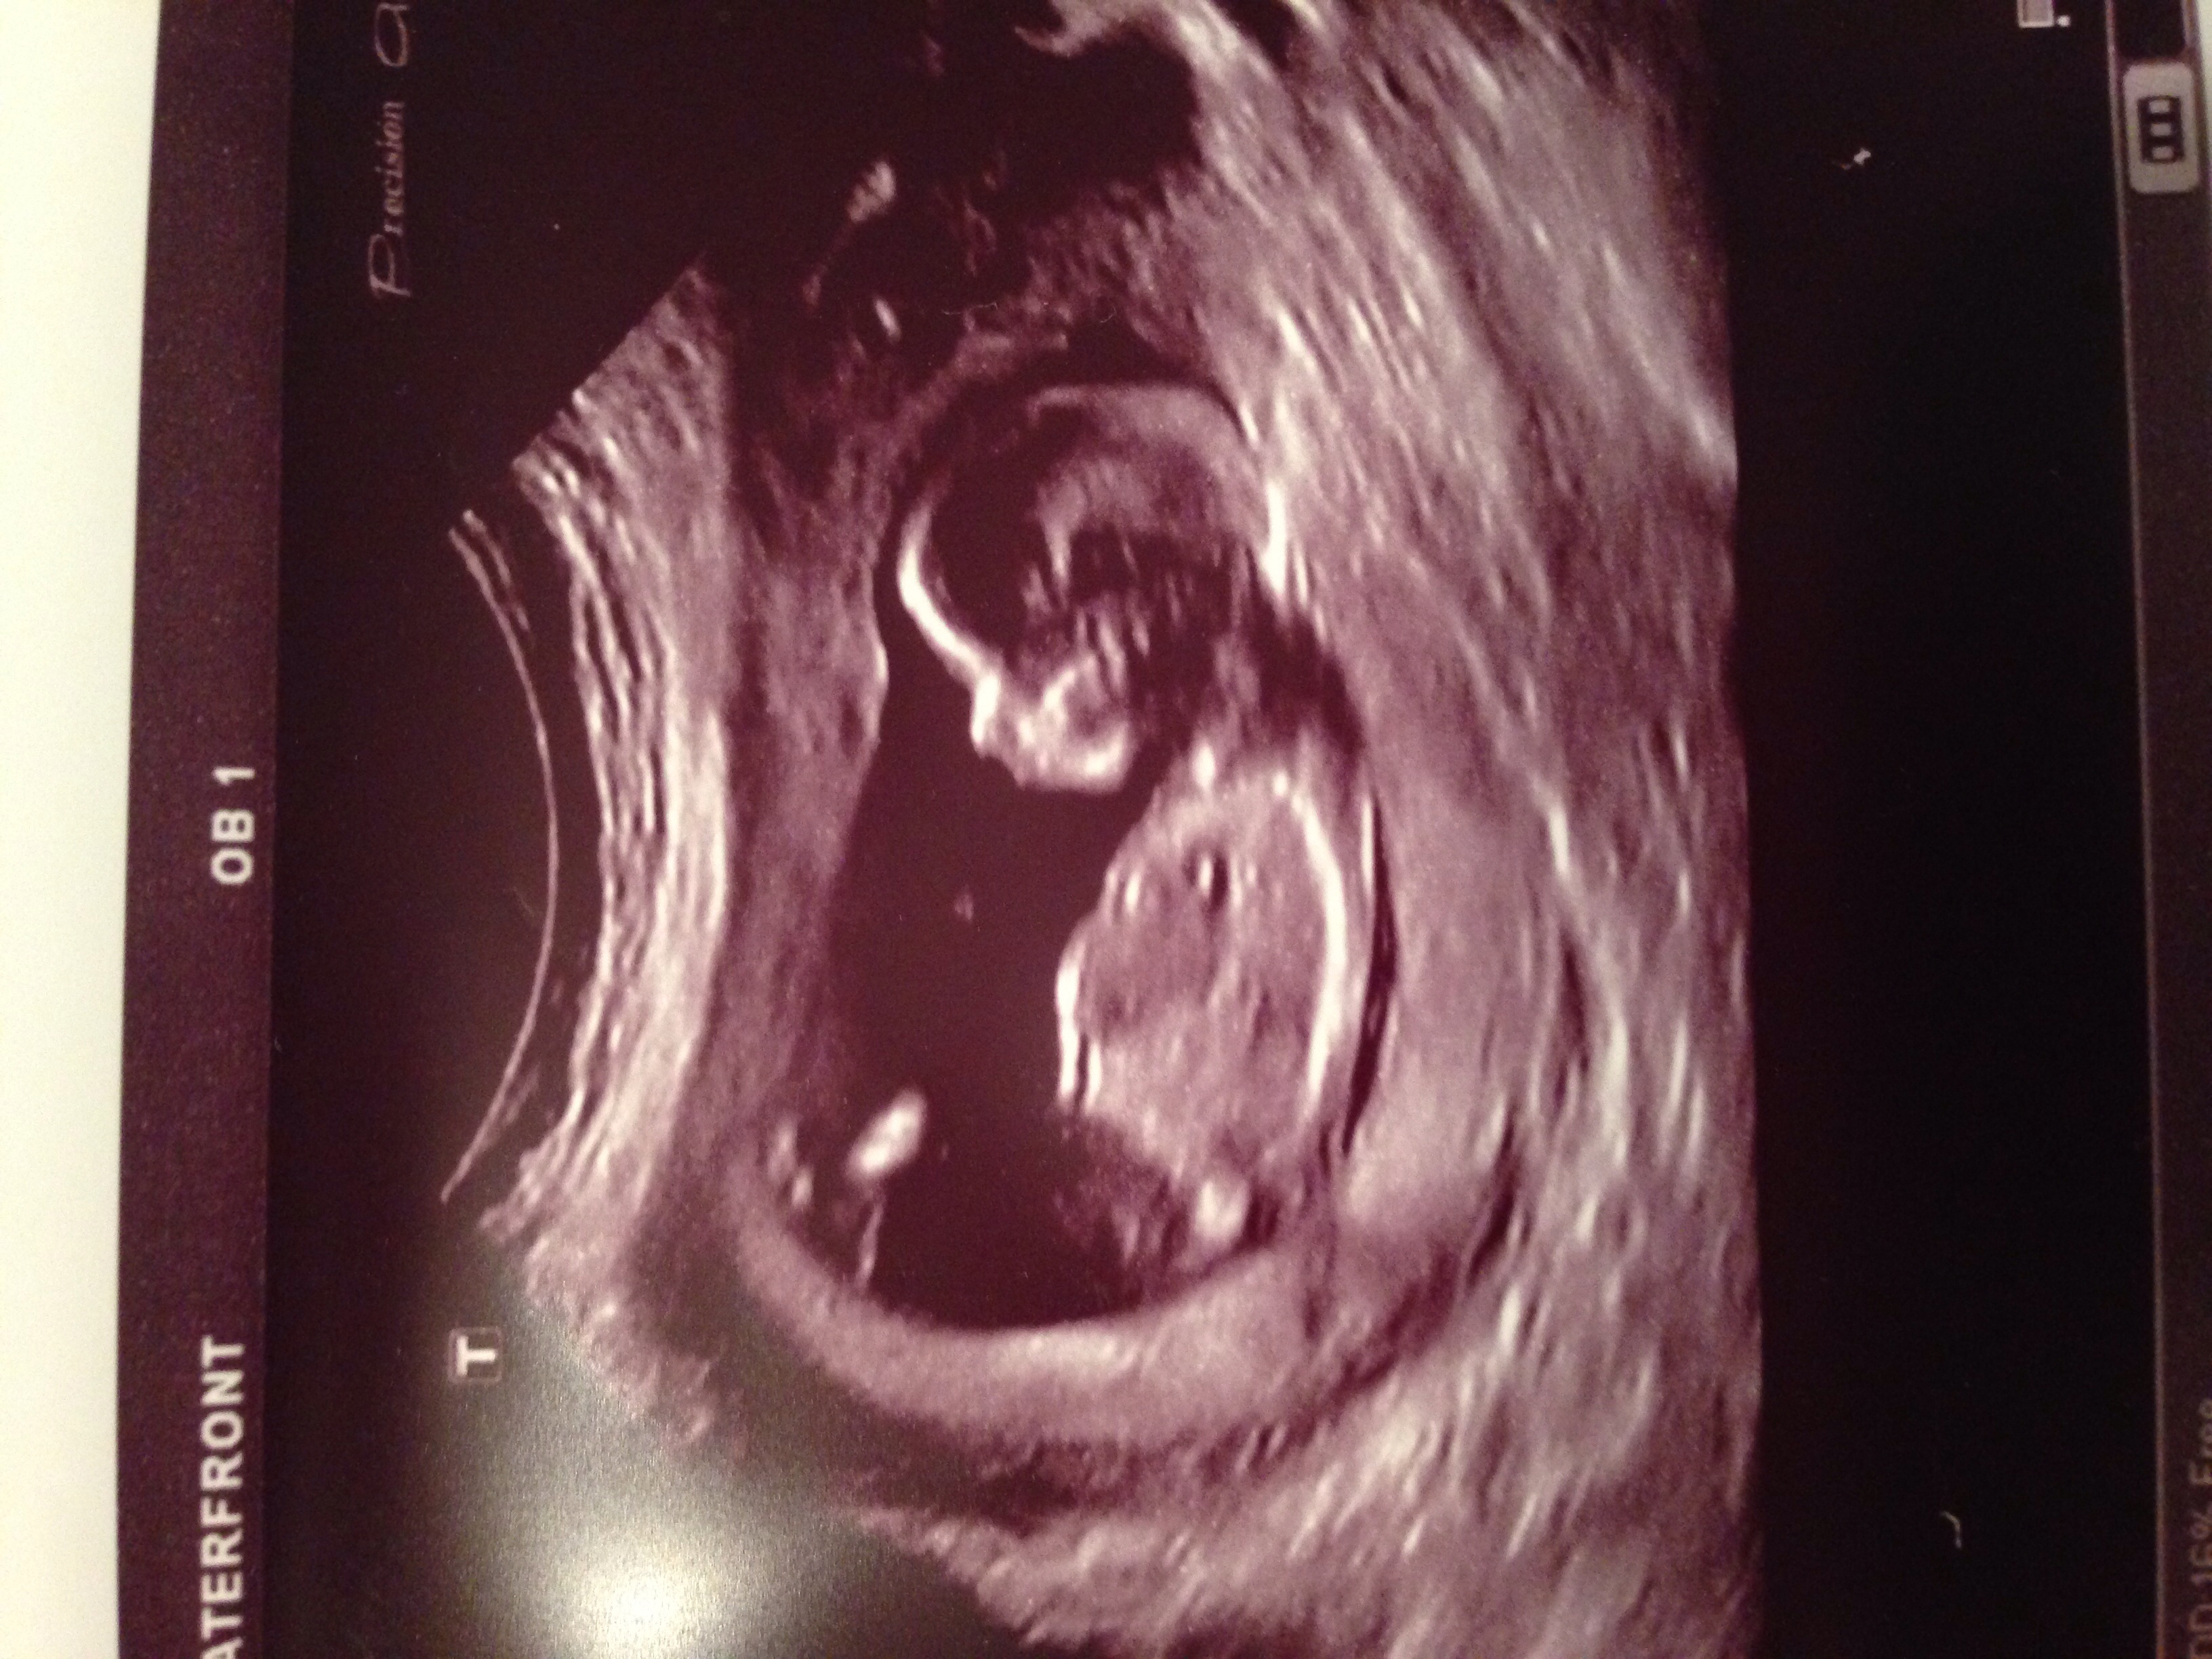

I'm not sure if any of these pictures have any gender clues, but could you please take a look and guess?! Thank you!!

But going by your pics... the first 2 aren't definitive, the 3rd looks very girly and the 4th looks sort of boyish.

im sayin boy goin by the last pic.